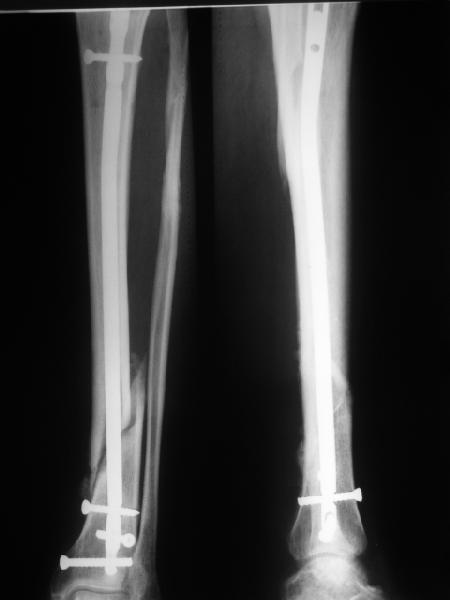

В приложении картинка пациента со сломанным внизу гвоздем. Начал лечение в другом учреждении. Еще и адвокат к тому же.

Динамизировали через 8 недель, а оно поползло больше, чем хотелось бы.